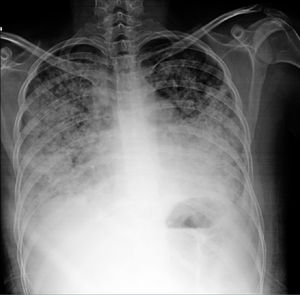

Pronóstico. Las series antiguas reportan una mortalidad de hasta el 50%; la serie más reciente reportó una mortalidad del 40%28. Si bien es una complicación poco común, la neumonitis lúpica durante el embarazo y en el postparto se ha asociado a desenlaces particularmente adversos29-31. El predominio de linfocitos en LBAV se asocia a evolución más favorable, mientras que el predominio de eosinófilos o neutrófilos se asocia a mayor mortalidad. Hasta en el 50% de los supervivientes persisten los infiltrados intersticiales y función respiratoria anormal con riesgo de progresión a neumonitis crónica intersticial3,14. En la figura 3 se muestran datos de neumonitis e hipertensión pulmonar.

Hombre de 22 años con hermano gemelo con lupus eritematoso sistémico, ambos con datos de síndrome de Schnitzler (cuadros intermitentes de fiebre, urticaria, dolor abdominal, angioedema, artritis), en los últimos 2 meses con disnea progresiva hasta la de mínimos, poliartritis, hipertensión, edema mecánico y en los días precedentes tos e incremento de disnea. A la exploración, con complejo de la pulmonar de Chávez y síndrome de condensación basal derecho; radiografía con datos de hipertensión pulmonar, 4 arcos, neumonitis basal derecha y derrame homolateral. Se realizó diagnóstico de neumonitis lúpica que se manejó con prednisona 0,5mg/kg/día y ciclofosfamida con adecuada respuesta.